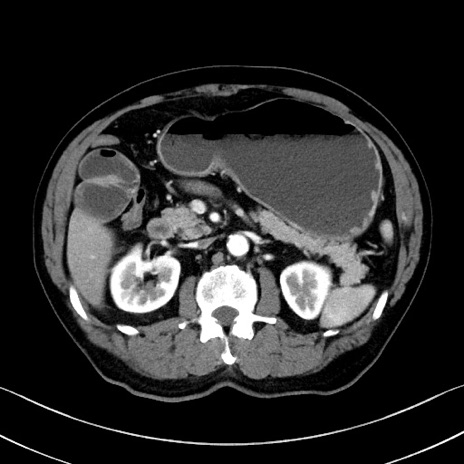

症例35(横断像)

【症例】70歳代 男性

【主訴】腹部膨満、嘔吐

【現病歴】昨日より腹部膨満感出現。本日増悪し、仙痛出現。嘔吐あり、受診。

【既往歴】糖尿病、胆摘後

【身体所見】BP 149/80mmHg、HR 74/min、BT 35.9℃、腹部:膨満、軟、圧痛なし。腸雑音減弱あり。上腹部正中切開瘢痕あり。

【データ】WBC 13500、CRP 1.72